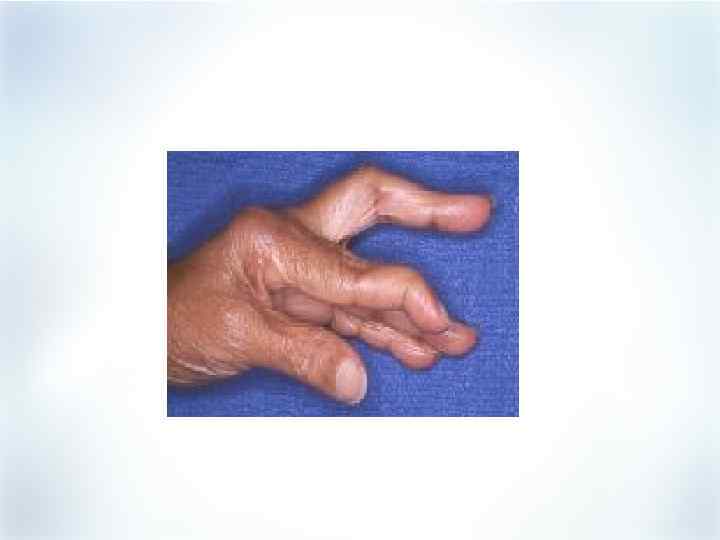

Суставные проявления РА Острый период § Припухлость суставов § Боль в суставах (утро, ночь) § Утренняя скованность § Ограничение подвижности § Характерная локализация ЧБС, ЧПС, ВАШ активность болезни § § Chen S, et al. Drug Topics. 2000; April 3: 47 -56. Отдаленные последствия Стойкое повреждение сухожилий, связок, хряща, костей Деформация суставов Вывихи суставов Функциональная недостаточность

Суставные проявления РА Острый период § Припухлость суставов § Боль в суставах (утро, ночь) § Утренняя скованность § Ограничение подвижности § Характерная локализация ЧБС, ЧПС, ВАШ активность болезни § § Chen S, et al. Drug Topics. 2000; April 3: 47 -56. Отдаленные последствия Стойкое повреждение сухожилий, связок, хряща, костей Деформация суставов Вывихи суставов Функциональная недостаточность